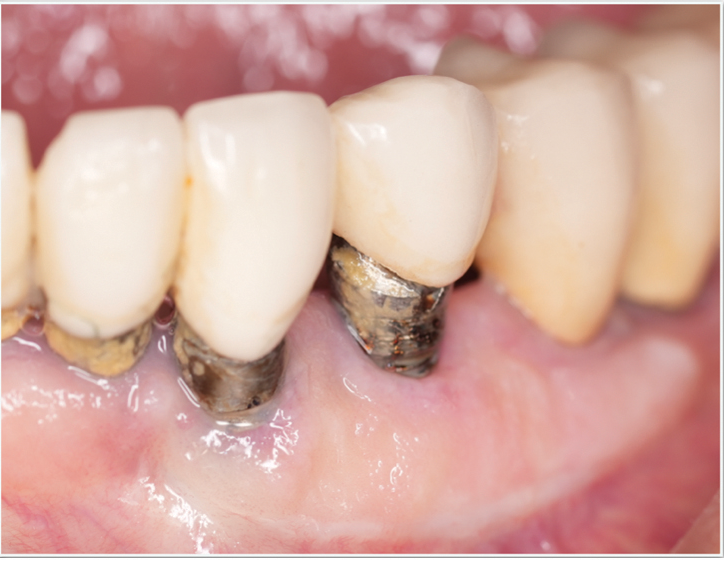

Fig 5 and Fig 6. Pre- (Fig 5) and post-treatment (Fig 6) photographs of a patient who received resective implant surgery to assess peri-implantitis at sites Nos. 14 and 15. Note the improved cleansability of the implants after surgery that opened the embrasure (Fig 6). The patient was placed on 3-month supportive peri-implant care post-surgery.

Figure 5

Figure 6

Surgical treatment encompasses both resective and regenerative approaches.41 During resective surgical therapy of peri-implantitis, the objectives are to remove excess granulation tissue, halt osseous cratering, and apically position the tissues, all of which may be done in combination with implantoplasty to smooth the threads of the roughened implant surface (Figure 5 and Figure 6).41 Conversely, regenerative surgical therapy involves the use of various combinations of bone grafts, membranes, and biologic materials to regenerate the lost implant-supporting structures.42